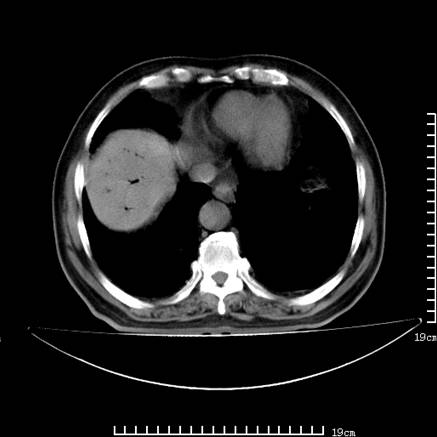

以下是引用lirenxiong在2008-7-19 22:01:00的发言:[br]胆总管结石并胆系感染,胆囊切除术后改变!左肾未见!左肾上腺增生肥大?请全腹扫描,增强!

以下是引用lirenxiong在2008-7-19 22:01:00的发言:[br]胆总管结石并胆系感染,胆囊切除术后改变!左肾未见!左肾上腺增生肥大?增强!